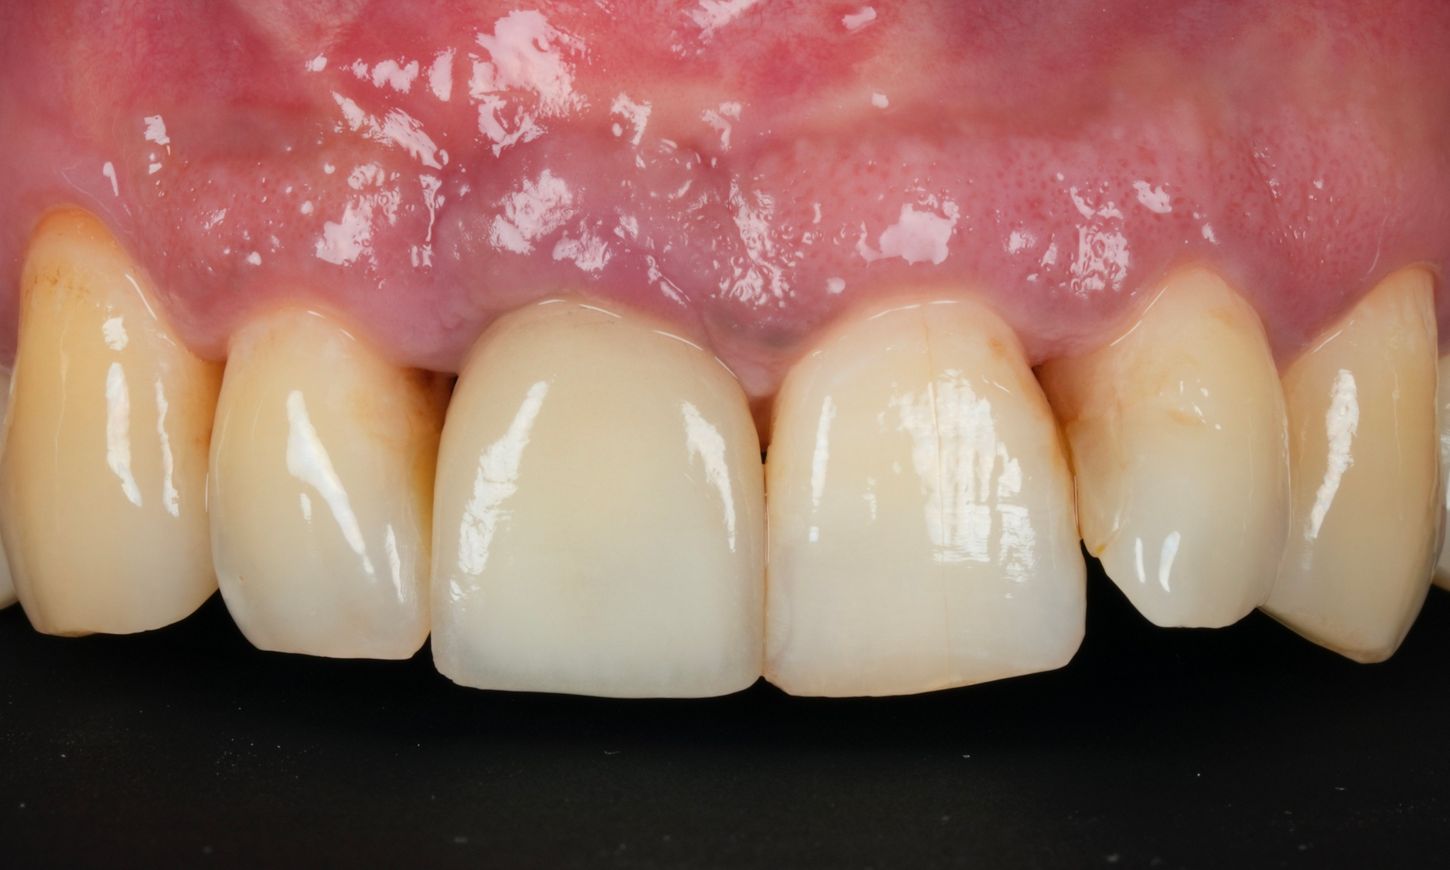

A 45-year-old male patient referred for treatment of peri-implantitis presented with recurrent inflammation, bleeding, and discomfort around the implant at tooth #11. His primary concern prioritized health over esthetics, with a strong desire to preserve the 1.5-year-old implant, even though full bone regeneration was not expected due to the implant position. He had no identifiable risk factors such as systemic diseases or smoking. His dental history included generalized stage III, grade C periodontitis, and extraction of tooth #11 due to a root fracture, followed by immediate implant placement and provisionalization (Fig. 1).

Fig. 1

Three months postoperatively, the Maryland bridge was removed. The soft tissue healing was satisfactory (Figs. 22-24).

A screw-retained zirconia provisional crown was delivered. The temporary restorations were milled for optimal fit and esthetics. The provisional was designed in an ideal way based on the digital scan during PI surgery (Figs. 25,26).

The referring dentist placed the definitive crown. The patient was very pleased with the result (Fig. 27)

Fig. 27